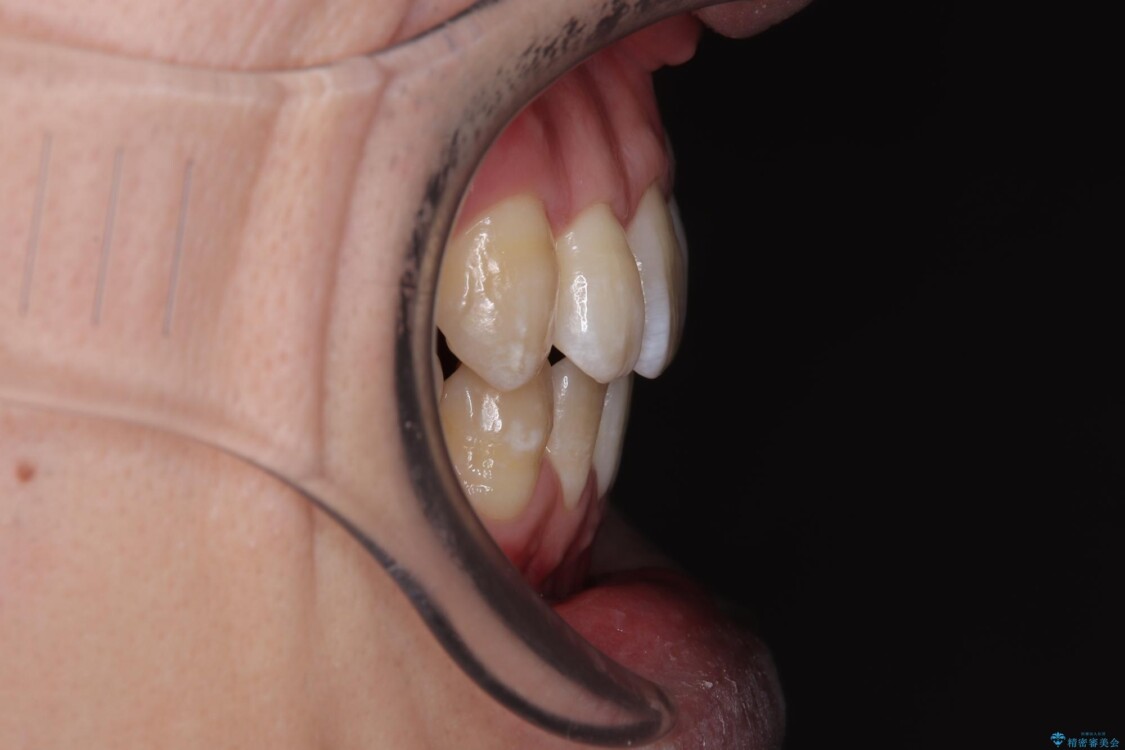

「横から見ると唇が前に出て見えるのが気になる…」 「マスクを外すのが恥ずかしい…」 そんな口元の突出感に悩まれてご来院された患者様。

治療前

• 口元の突出感を改善!目立ちにくいワイヤー矯正で自信を持てる自然な横顔に 治療前画像